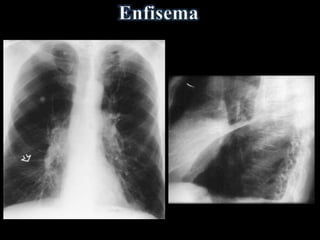

• Rebaixamento diafragmático(Costela: 11a ou 12a posterior; 7a anterior) • Retificação da cúpula • Coração alongado e verticalizado (em gota), diâmetro transverso < 11,5 cm • Aumento do tórax no diâmetro AP (em barril) • Aumento do espaço claro retroesternal (>2,5cm) • Aumento da Transparência Pulmonar ENFISEMA: • Bolhas - Área de maior radiotransparência >1cm, avascular, podendo estar delimitada por fina linha branca - Coalescência de alvéolos rotos • Atenuação da trama vascular periférica e proeminência dos vasos hílares